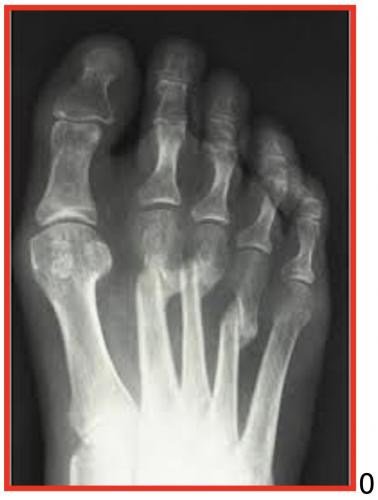

LA BUNIONETTE – QUINTUS VARUS- BUNION TAYLOR

La Bunionette (ou quintus varus) est une déformation du cinquième rayon du pied. Cette déformation angulaire est ?? l’origine d’un conflit anormal avec la chaussure créant une zone d’hyper appui douloureux qui est liée :

À des causes externes : marche sur le versant latéral du pied, chaussure rigide...)À des causes internes : anomalie de la forme du 5 éme métatarseTuméfaction douloureuse sur le bord externe de la 5 éme MTP

La bursite aiguë gène considérablement le chaussage, la situation peut s’aggraver, rendant le chaussage de plus en plus difficile.

QUE FAIRE ?

RADIOGRAPHIES DU PIED EN CHARGE FACE ET PROFIL